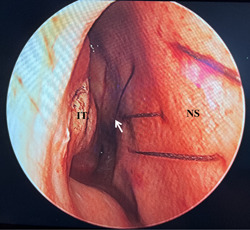

Case report: A 31-year-old female patient underwent suture removal 14 days after septoplasty and developed left-sided epistaxis 6 h after suture removal. To safely and effectively relieve the patient from epistaxis, the cauterization of the left PSA was performed under general anesthesia. However, 24 h after the first surgical hemostasis, the patient experienced epistaxis again in the right nasal cavity. We have reviewed the patient's sinus computed tomography again and found a rare variant of PSA, which is the right-sided PSA passing through a bony canal in the left-sided nasal septum.

Discussion: The variant of PSA well explained the failure of the first hemostatic surgery. Therefore, we again performed a cauterization of the right-sided PSA, after which the patient recovered and no further epistaxis occurred.